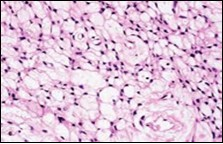

Figure 6.Soft tissue perineurioma with foci of spindle cells with wavy nuclei and an admixture of myxoid and collagenous stroma 15.